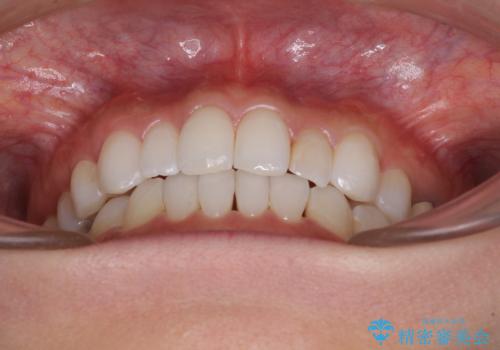

軽度の叢生をインビザライン・ライトで解消

- 前歯が気になるとのことで来院された患者様です。

歯列不正は軽微であったため、インビザライン・ライトにより、費用を抑えて矯正治療を行うこととしました。

短期間で気になる前歯の歯列を改善することができました。